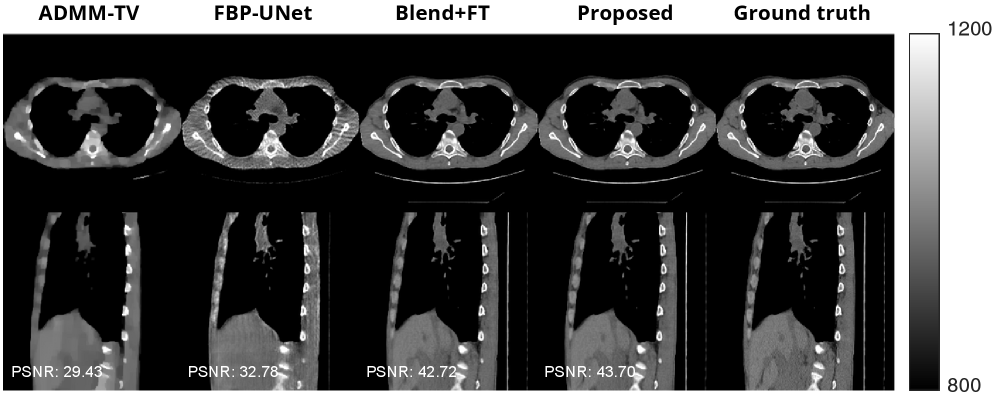

Figure 7 shows visual results of 8-view CT reconstruction on the AAPM dataset with our proposed method and some comparison methods. Compared to the result with DiffusionBlend (fine-tuned from a checkpoint pretrained on natural images), our method is able to preserve more details, such as bone artifacts and blood vessels of a lung.

Refer to caption

Figure 7: Results of our proposed method and comparison methods for 8-view 3D CT reconstruction on AAPM dataset. The top row shows an axial slice and the bottom row shows a sagittal slice from each reconstructed volume.